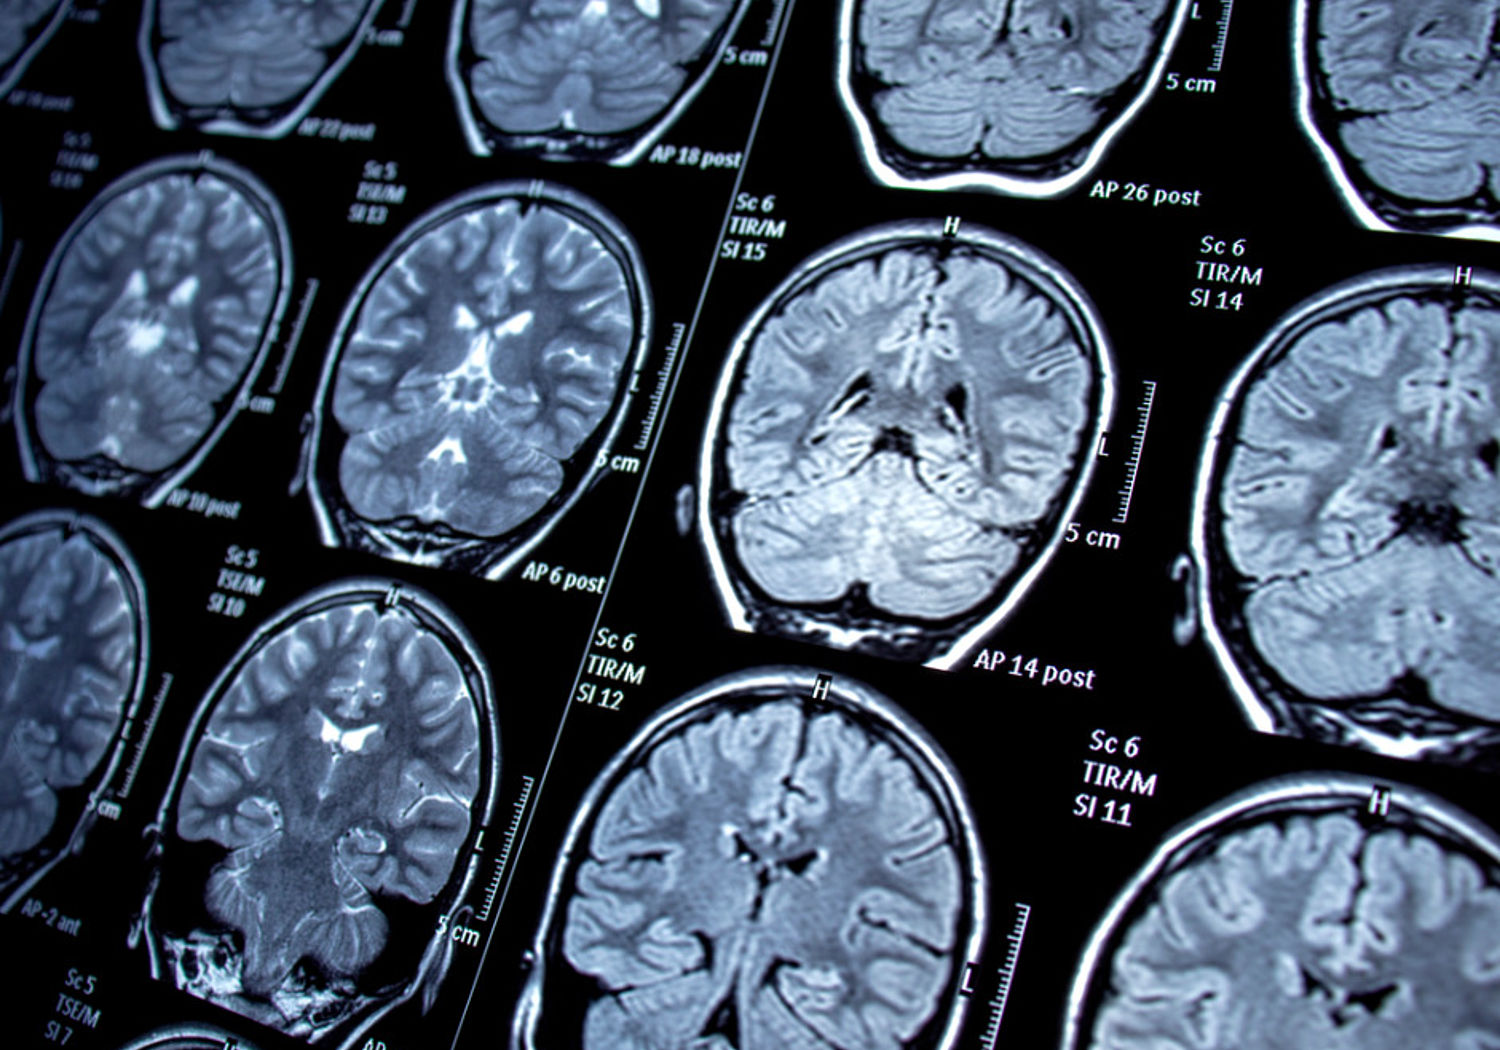

MRI scans of the brain

Magnetic resonance imaging (MRI) uses radio waves and large magnetic fields to help identify conditions ranging from damaged ligaments to cancer. Around 40 million MRI scans are performed each year in the EU, but the size and cost of scanners means that not all European citizens have equal access to this form of medical diagnosis.